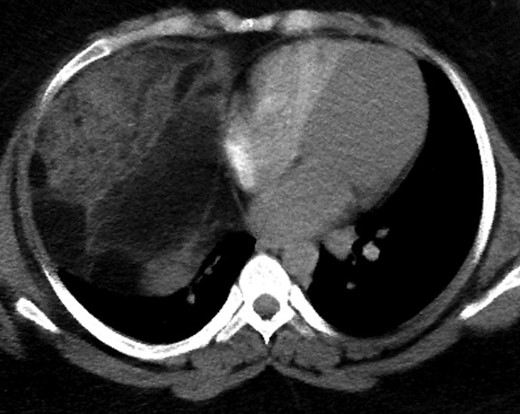

A 28-year-old asymptomatic obese female presented to the bariatric clinic for weight reduction surgery. During the routine bariatric preoperative evaluation, examination revealed decreased breath sounds bilaterally and dullness to percussion in the anterior chest. On X-ray, widening of the mediastinum with possible intrathoracic mass was identified and the patient was referred to thoracic surgery. Further laboratory investigation of common tumor markers, such as ABG, AFP, HCG, CA 19.9 and CEA, were all negative along with chemistry and hepatic panels. CT imaging was performed and revealed a large heterogeneous anterior mediastinal mass with fat and soft tissue. With possible differential including thymolipoma, liposarcoma and germ cell tumors, further imaging of the abdomen, brain and bones was performed and did not show any evidence of metastasis. CT-guided biopsy revealed a well-differentiated sclerosing variant liposarcoma with cellular-spindled areas. The cells were positive for CD34, desmin, S100 and MDM2. They were negative for SMA, CD117 and DOG1 (Figs 1–5).

Liposarcoma predominantly presents in the deep soft tissue of the limbs and the retroperitoneum. Although the overall anatomic distribution may be widespread, primary liposarcoma of intrathoracic origin is a very rare entity with few reported cases in the international literature [1]. Liposarcoma of the anterior mediastinum is even rarer as it is more commonly found in the posterior mediastinum [3]. Most of these masses are diagnosed incidentally or worked up secondary to compression symptoms from intrathoracic structures: dyspnea, tachypnea, wheezing, chest pain, SVC compression and voice hoarseness. These tumors are most commonly discovered during chest X-ray with a finding of widened mediastinum. On CT, a low attenuation signal between −50 and −150 HU is indicative of fatty tissue while greater signal intensity indicates soft tissue or tissue necrosis [4]. Of course, these indicators cannot be used as a diagnosis and differentials for such a mass must include thymolipoma, teratoma, germ cell tumor, lymphoma, herniated peritoneal fat and diaphragmatic hernia [5].